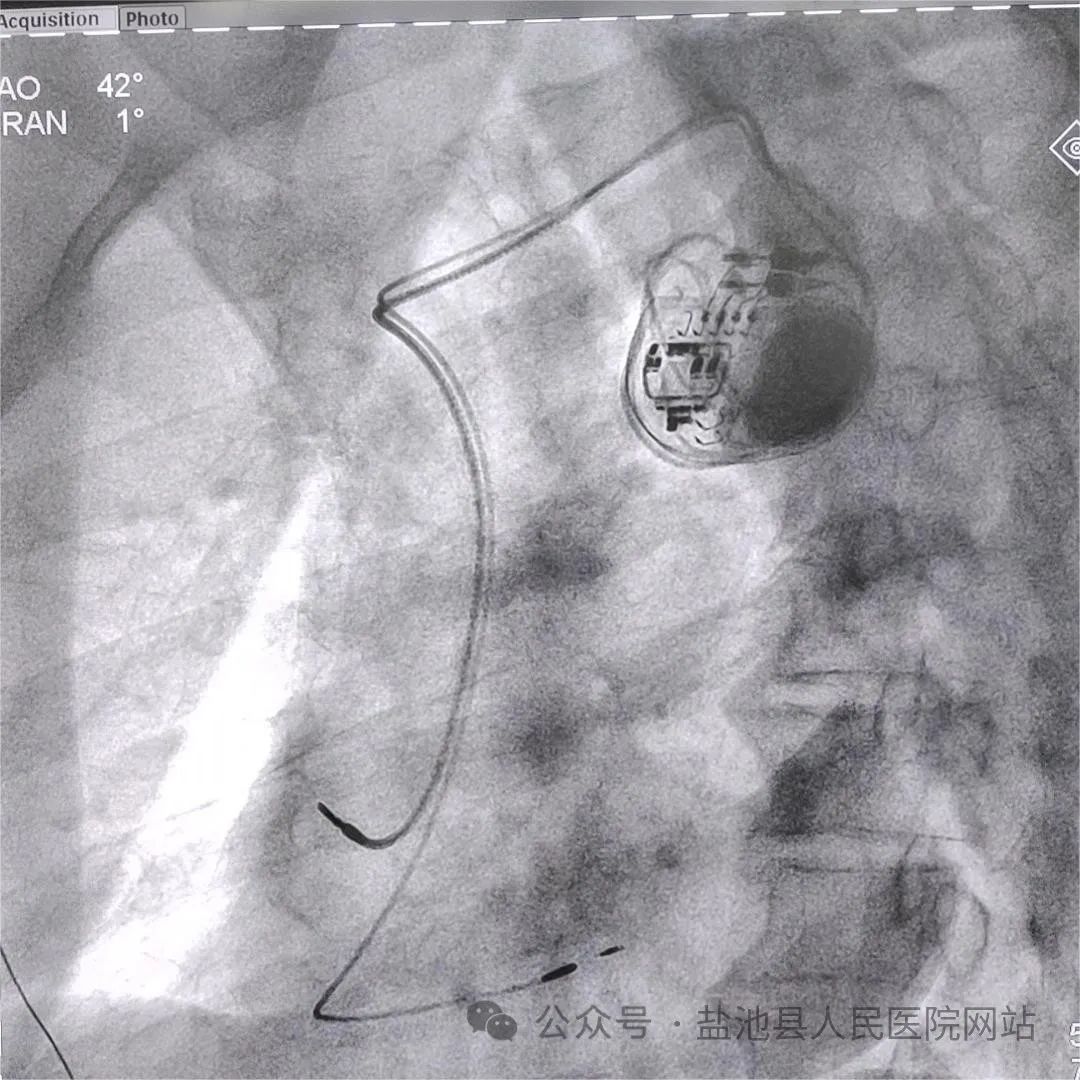

团队成员精心准备,精诚合作,精细操作,精准定位,通过左锁骨下静脉穿刺,在X线及多导电生理仪指导下精确找到患者的左束支起搏区域,并将电极从右心室间隔侧精准旋入到左心室内膜下的左束支区域,从而使电刺激信号通过该路径向下传导,手术过程顺利,左束支电位明显,起搏各参数满意,电极固定牢固,手术取得圆满成功。